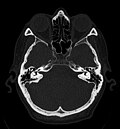

Craniale Computertomographie Abgebildet sind Felsenbein und Nasennebenhöhlen. Aufgrund der hohen Auflösung der Aufnahme des verwendeten 64-Zeilen-CTs sind selbst die Gehörknöchelchen erkennbar. -